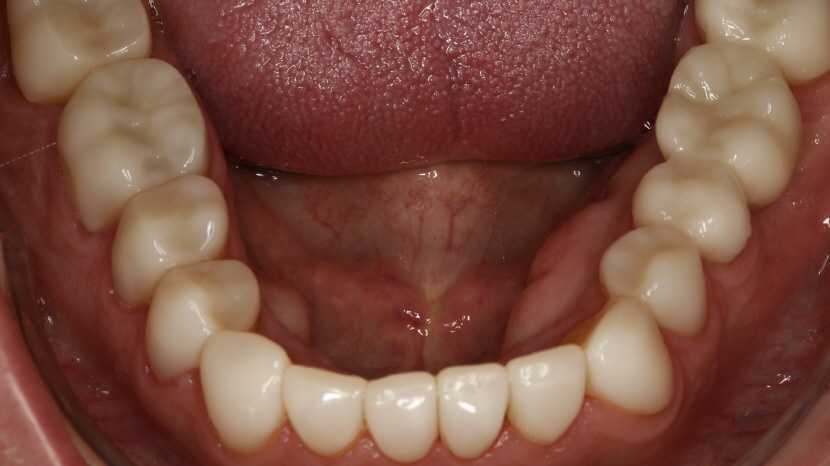

• Aufbissansicht nach Therapie des Unterkiefers

Die Brücke im Oberkiefer links, wie auch die Brücke im Unterkiefer rechts, wurden durch den Zahntechniker (N. Lanfranconi, Zürich) volldigital aus Zirkon hergestellt